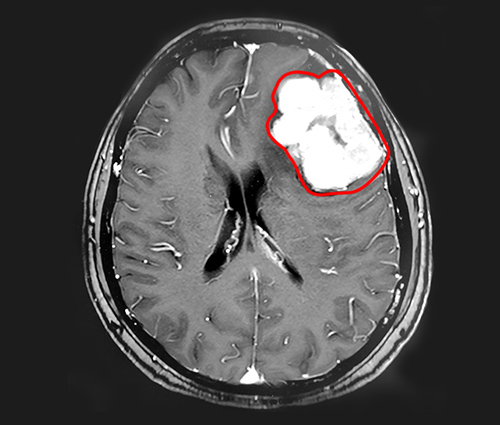

▲MRI影像顯示,患者左側(cè)額葉有體積較大的腫瘤

在藍(lán)十字,程阿姨的頭顱核磁共振影像顯示,患者左側(cè)額葉有巨大團(tuán)塊狀異常信號(hào),大小約5.5*4.3*4.8cm,臨近的左側(cè)側(cè)腦室受壓變窄。在這個(gè)腫瘤周?chē),還有多枚體積較小的腫瘤,具有腦膜瘤的典型特征。